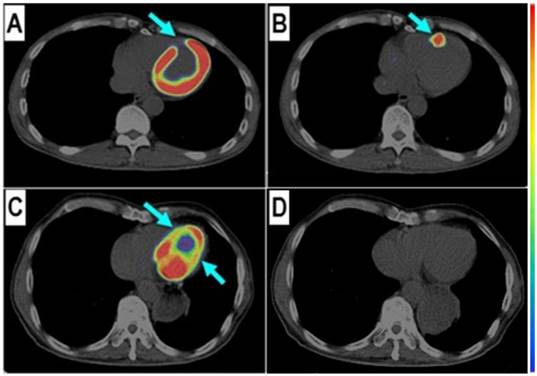

68Ga-PRGD2 PET/CT in evaluation of MI. 68Ga-PRGD2 uptake was evaluated 30 min after intravenous injection when the blood pool background and normal distribution in myocardium were relatively low (Figure 1). By referring to the matched 99mTc-MIBI and 18F-FDG images, 68Ga-PRGD2 uptake was found at or around the ischemic regions in 20 of the 23 MI patients (Figure 2). The uptake was in patchy form with pSUVs of 1.94 ± 0.48 (mean ± standard deviation [SD]; range, 0.62-2.69), which were significantly higher than the mean SUVs of the remote normal myocardium (mean ± SD, 0.94 ± 0.34; range, 0.28-1.45; P < 0.001) and the lesion to normal myocardial background ratios were calculated as 2.33 ± 1.04 (mean ± SD; range, 1.42-5.18).

Figure 1

68Ga-PRGD2 uptake was found in the infarct region in a patient 6 days after the event but not presented in another patient 2 years after the myocardial infarction. In a 58-year-old man at the 6th day after the event, the 18F-FDG defect area (A, arrow) at the anterior septum showed definite 68Ga-PRGD2 accumulation (B, arrow) with a pSUV of 1.79. In a 69-year-old man at 2 years after the myocardial infarction, the anterior septum and inferior lateral wall with decreased 18F-FDG uptake (C, arrow) had no 68Ga-PRGD2 accumulation (D).

In this group of patients, higher 68Ga-PRGD2 uptake was found approximately 1 week after the MI event and remained high in the patients 2.5 months post-MI (Figure 3). In 15 MI patients within 4-75 days after the attack when the 68Ga-PRGD2 uptake seemed to be in a plateau (Figure 3), the uptake levels were significantly correlated with the maximum diameters of the infarction regions measured on the 99mTc-MIBI cardiac perfusion imaging (r=0.748, P=0.001) (Figures 2 and 4).

Among the three patients without significant 68Ga-PRGD2 accumulation at the cardiac region, one patient was on the third day after a slight MI attack without ST-elevation on the ECG, whereas the other two patients were 1-2 years post-MI without any related symptoms (Figure 1 C and D).